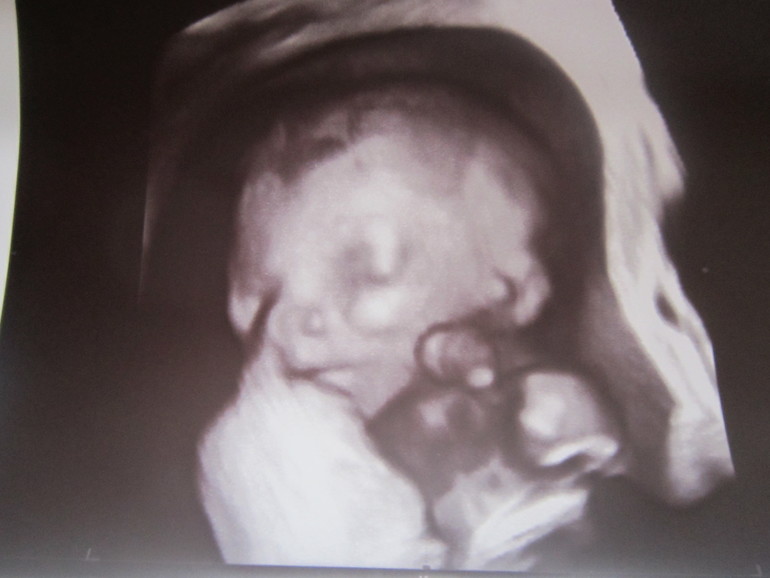

Никак не хотела показывать личико, постоянно утыкалась в плаценту))Она там на ней как на подушке))Но потом все таки удалось!))Я не могла оторвать глаз))Наверно для всех их детки, даже в утробе, кажутся самыми красивыми))

Щечки...)))